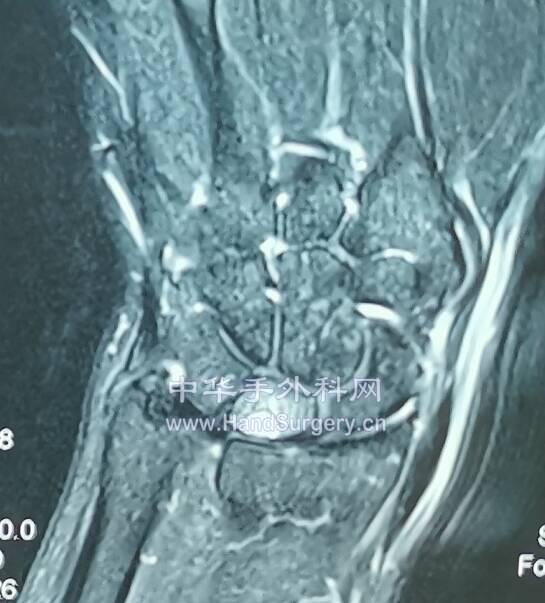

月骨坏死III期

微信截图_20200620170439.png

微信截图_20200620170520.png

微信截图_20200620170555.png